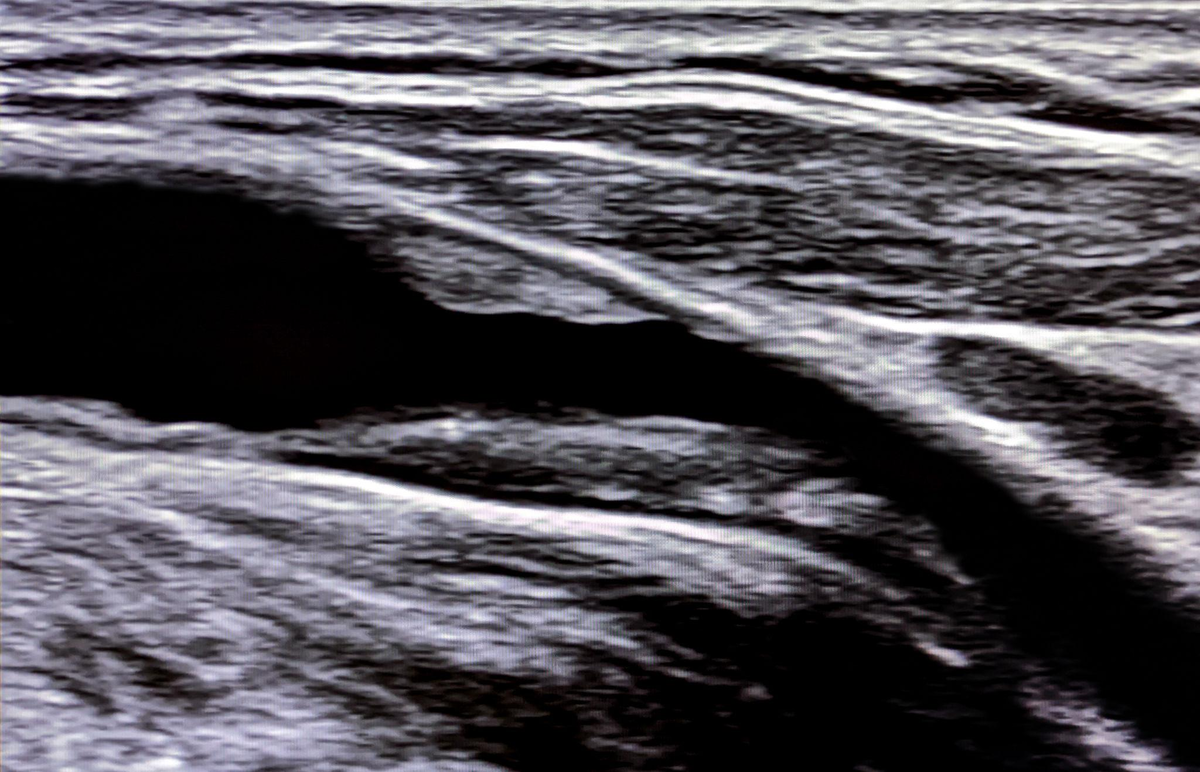

Здесь бляшка создает стеноз побольше, чем 30%